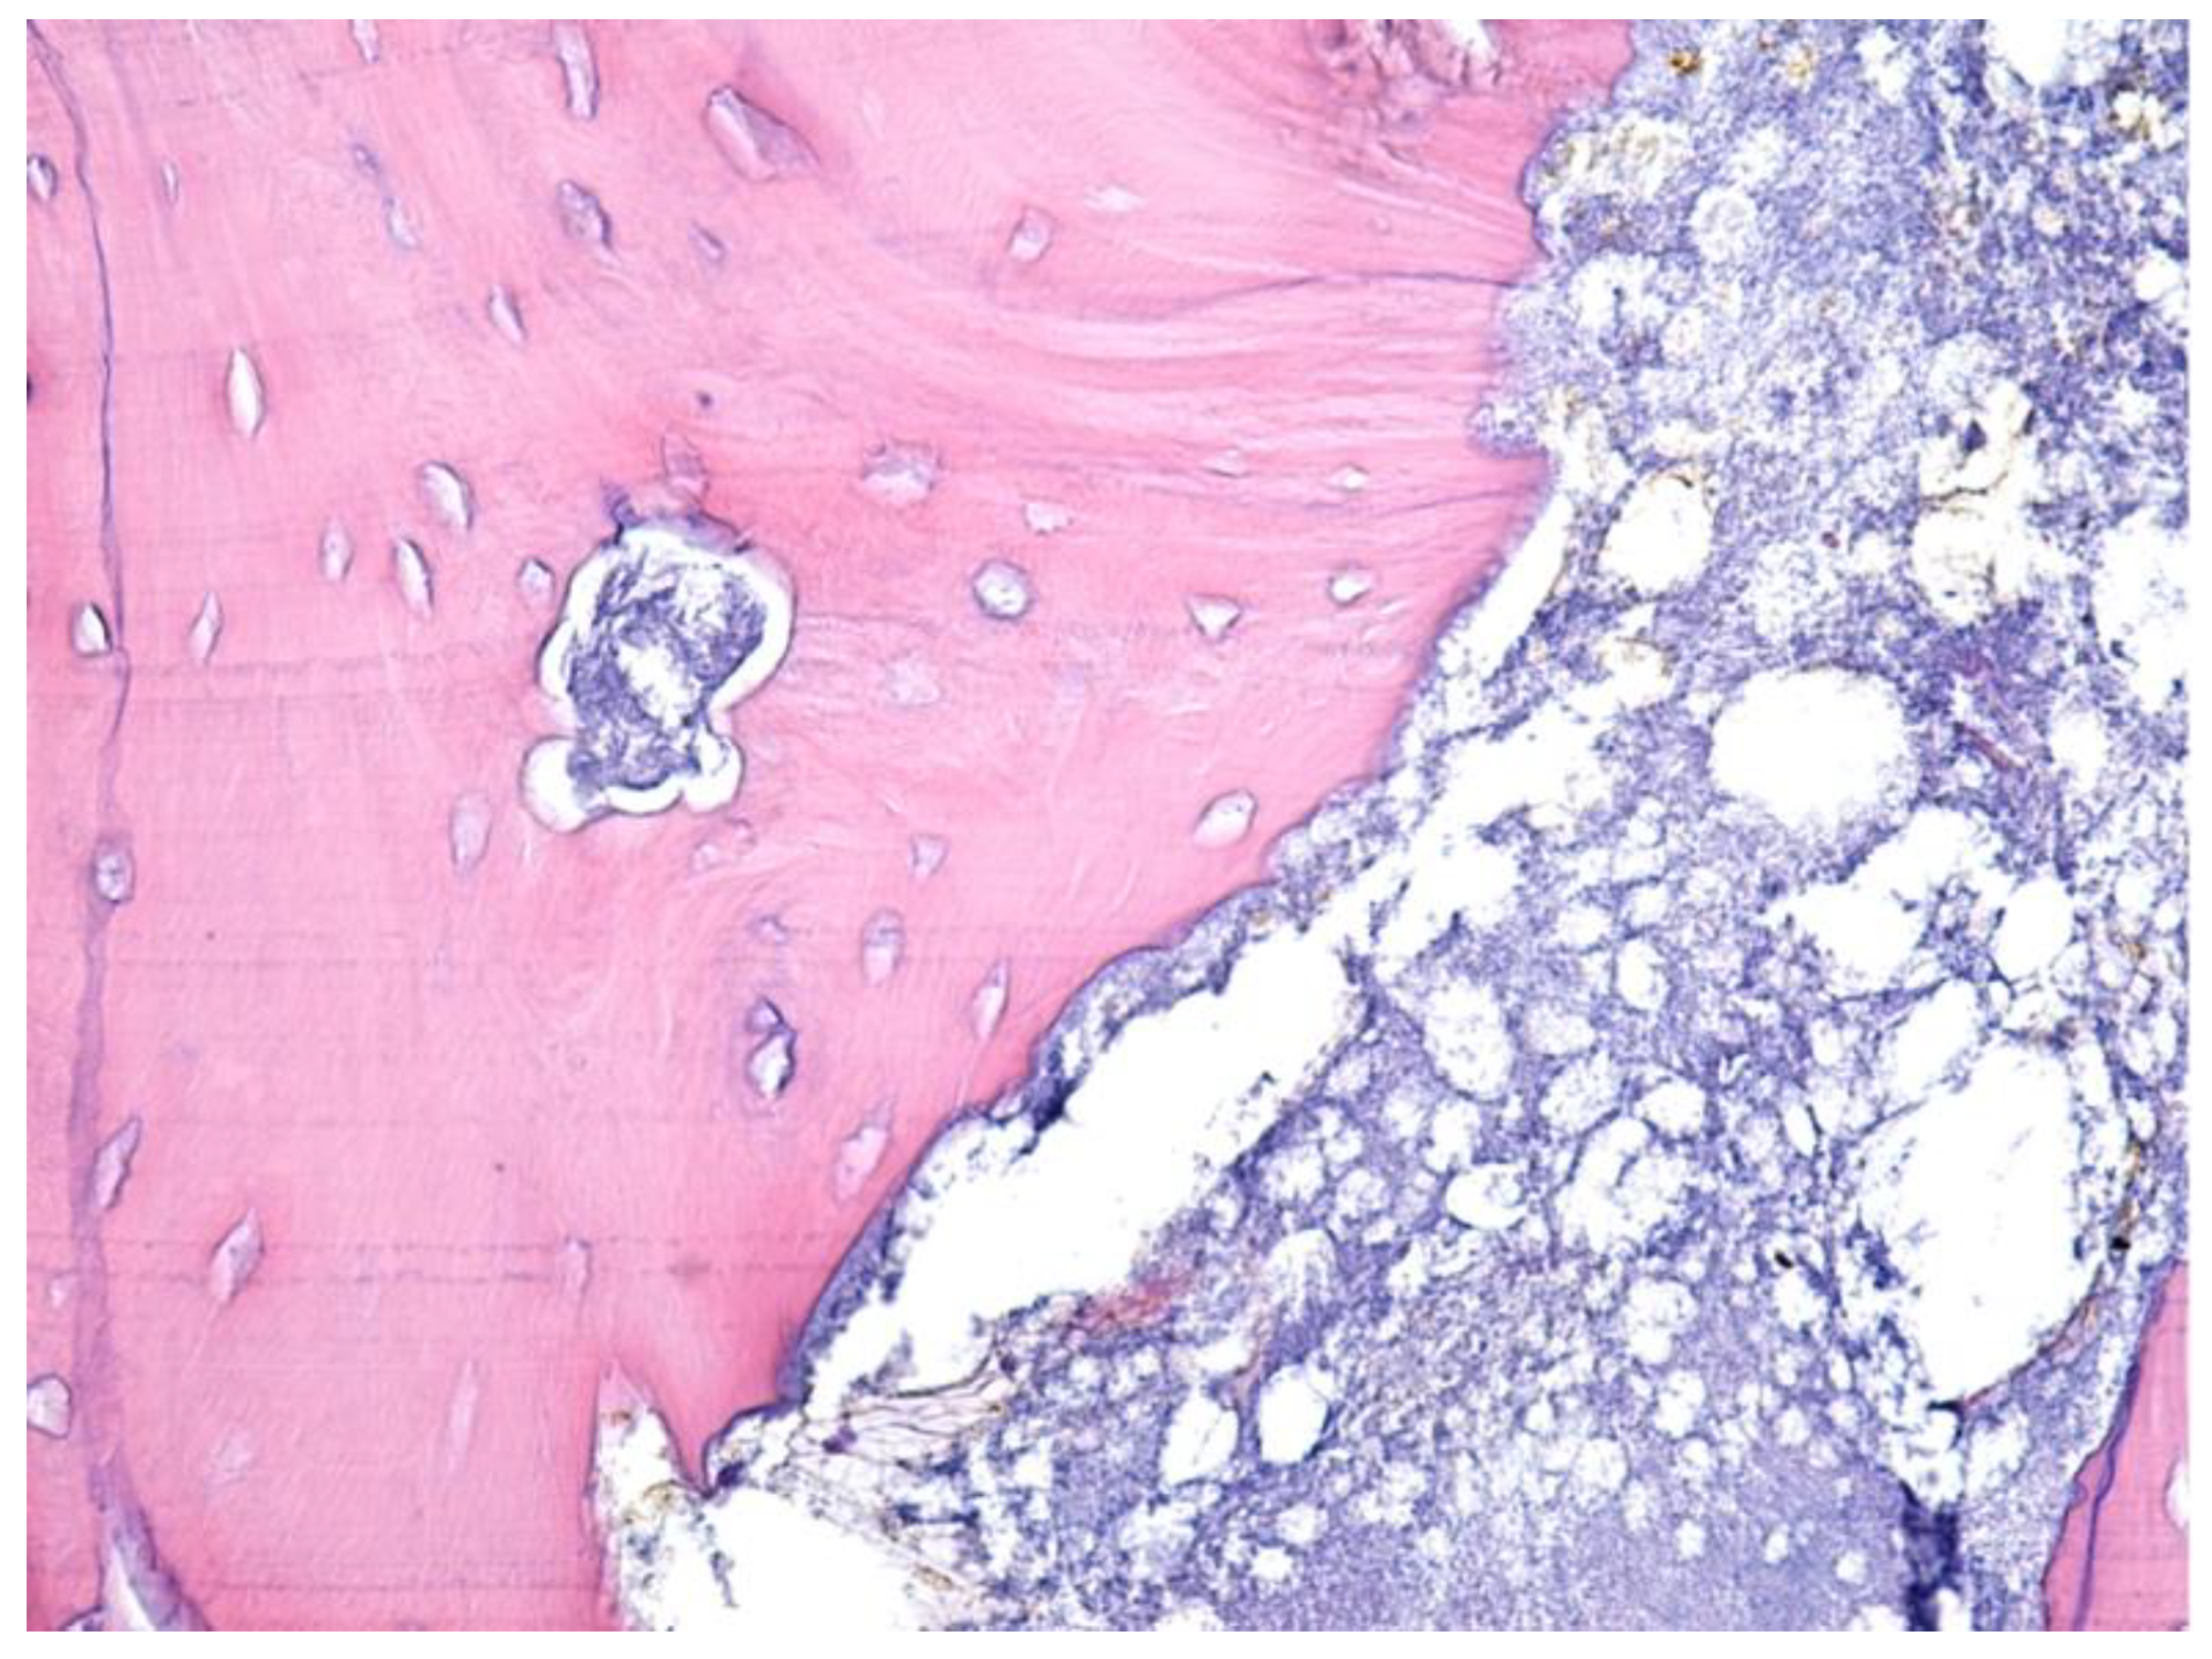

- Paparella, M.; Brandizzi, D.; Santini-Araujo, E.; Cabrini, R. Histopathological features of osteonecrosis of the jaw associated with bisphosphonates. Histopathology 2011, 60, 514–516. [Google Scholar] [CrossRef]

- Favia, G.; Pilolli, G.P.; Maiorano, E. Histologic and histomorphometric features of bisphosphonate-related osteonecrosis of the jaws: An analysis of 31 cases with confocal laser scanning microscopy. Bone 2009, 45, 406–413. [Google Scholar] [CrossRef] [PubMed]